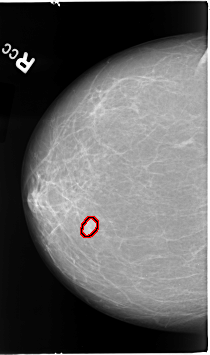

B_3067_1.RIGHT_CC

RIGHT_CC LINES 4608 PIXELS_PER_LINE 2720 BITS_PER_PIXEL 12 RESOLUTION 50 OVERLAY

FILE: B_3067_1.RIGHT_CC.OVERLAY

TOTAL_ABNORMALITIES 1

ABNORMALITY 1

LESION_TYPE MASS SHAPE LOBULATED MARGINS CIRCUMSCRIBED-ILL_DEFINED

ASSESSMENT 4

SUBTLETY 5

PATHOLOGY MALIGNANT

TOTAL_OUTLINES 1

BOUNDARY